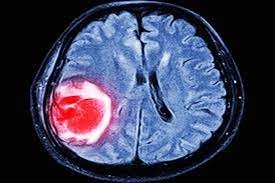

O Glioblastoma Multiforme (GBM) é o tipo mais comum e agressivo de tumor cerebral maligno que se desenvolve a partir das células gliais do cérebro. Ele é caracterizado por múltiplos focos de tumor no cérebro e crescer rapidamente, infiltrando os tecidos circundantes. A causa exata do GBM é desconhecida, mas acredita-se que seja causada por uma combinação de fatores genéticos e ambientais.

O diagnóstico de GBM geralmente é feito com base em uma combinação de histórico médico, exame físico, exames de imagem e testes de laboratório. Os exames de imagem que podem ser usados ??para diagnosticar GBM incluem tomografia computadorizada (TC), ressonância magnética (MRI) e tomografia por emissão de pósitrons (PET). Os testes de laboratório que podem ser usados ??para diagnosticar GBM incluem um exame de sangue e um exame de líquido cefalorraquidiano (LCR).